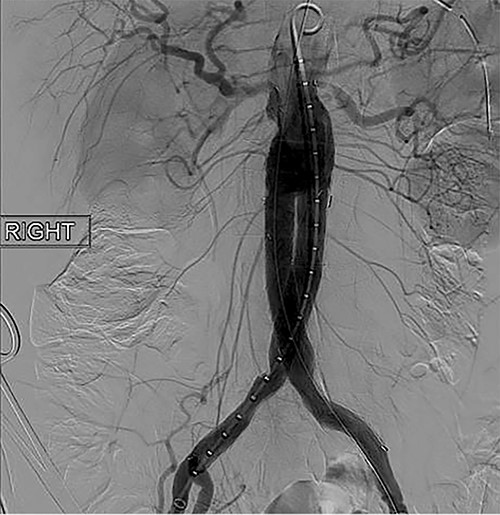

To obtain vascular access, bilateral cutdown technique was used to dissect the common femoral arteries. The femoral arteries were cannulated, the patient heparinized, and an arteriogram obtained (Fig. 2). The main body of the graft was deployed without complication, followed by bilateral iliac limb extensions. The graft was treated with the Molding & Occlusion Balloon (MOB) at all attachment points. Repeat arteriogram demonstrated excellent technical result without evidence of endoleak (Fig. 3). Protamine was administered for reversal of heparin, bilateral groin incisions were closed, and nasogastric tube (NGT) was left in place on low intermittent wall suction. Aspirin/Plavix therapy was continued.

Intraoperative fluoroscopy illustrating infra-renal, abdominal aortic aneurysm prior to graft placement.